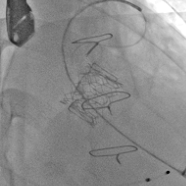

术前经详尽评估患者病情,通过CT重建测量瓣环直径、左室流出道面积。结合之前外科换瓣手术入路,最终决定采用经心尖途径行二尖瓣“瓣中瓣”手术,患者既往植入27#爱德华猪瓣,选用25# Renato®球扩式瓣中瓣。手术过程顺利,瓣中瓣植入位置理想,功能表现出色,左室造影及经食道超声观察无明显瓣中及瓣周反流。二尖瓣峰值流速由术前2.1m/s降至1.0m/s,平均跨瓣压差由7.2mmHg降至1.8mmHg。

瓣中瓣术后